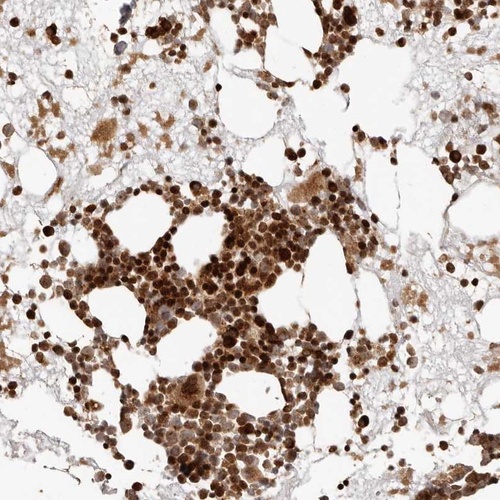

Immunohistochemical staining of human bone marrow shows strong cytoplasmic and nuclear positivity in bone marrow poietic cells.